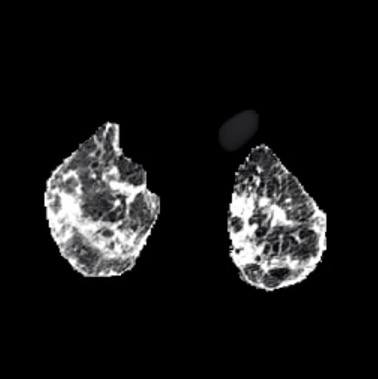

In the field of medical imaging, particularly in tasks related to early disease detection and prognosis, understanding the reasoning behind AI model predictions is imperative for assessing their reliability. Conventional explanation methods encounter challenges in identifying decisive features in medical image classifications, especially when discriminative features are subtle or not immediately evident. To address this limitation, we propose an agent model capable of generating counterfactual images that prompt different decisions when plugged into a black box model. By employing this agent model, we can uncover influential image patterns that impact the black model's final predictions. Through our methodology, we efficiently identify features that influence decisions of the deep black box. We validated our approach in the rigorous domain of medical prognosis tasks, showcasing its efficacy and potential to enhance the reliability of deep learning models in medical image classification compared to existing interpretation methods. The code will be publicly available at https://github.com/ayanglab/DiffExplainer.